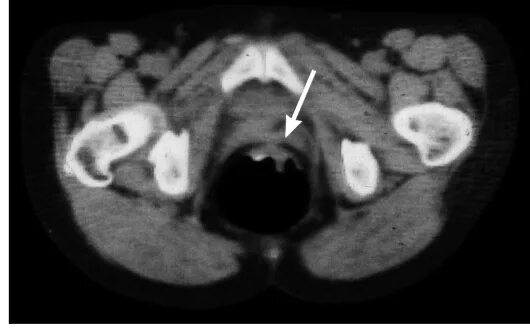

Рак прямой кт